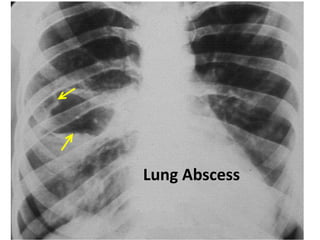

Lung Abscess

Cavitary tumour with air-fluid level

Cavitary lesion